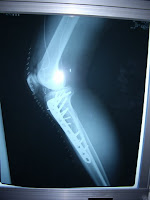

Two years ago - when Okaasan was still safely far away from us in Saitama - Yujiro had a big skiing accident and did a nasty compound fracture to his knee and leg. He had major surgery and now has two plates and 16 pins in his body.

He wants to go to Kutchan Hospital on Monday so the doctor can take a look and think about removing all the pins maybe in April. Which is all great.